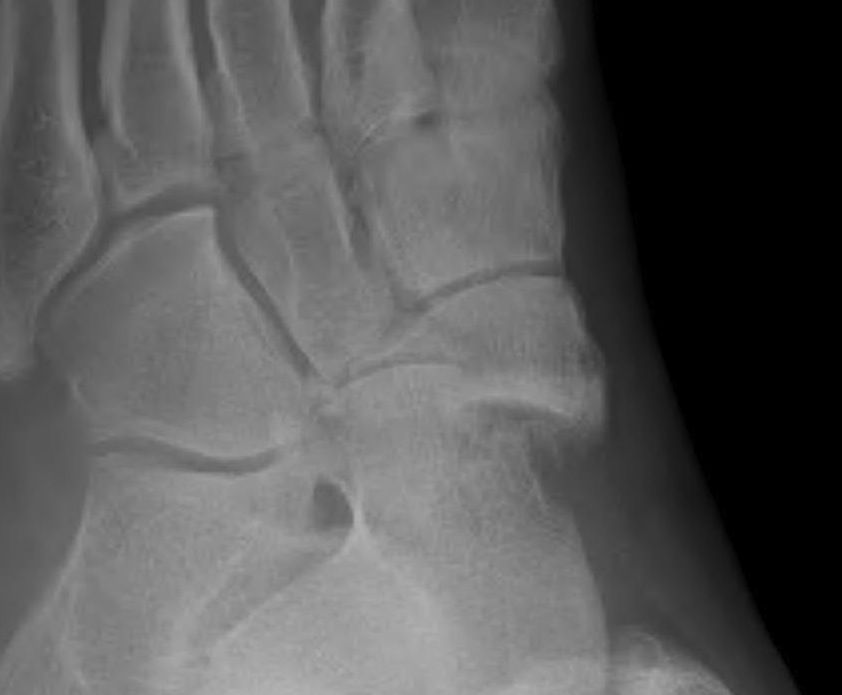

Imaging

Acute, minimally displaced navicular fracture

Acute displaced navicular fracture